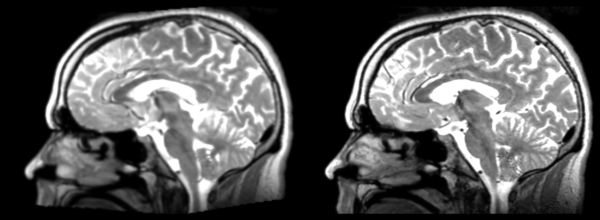

Affine

- 53-t2 -> 31-t1 = aff1

- aff1 -> 53-t2 = aff2

The image shows these side by side. The are nearly the same except for the loss of fine detail.